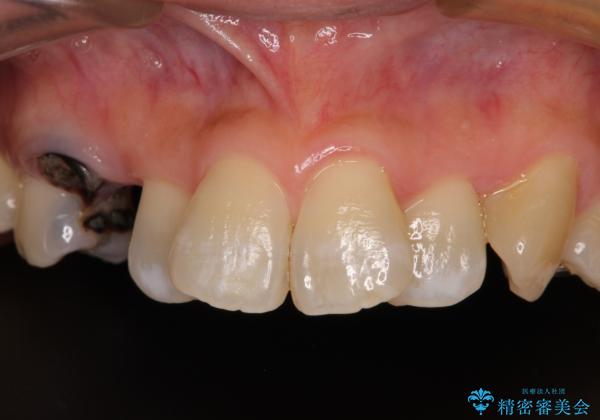

崩壊した歯は全て抜去し、他人から見える位置の歯はセラミッククラウンが装着され、整った口腔環境となりました。